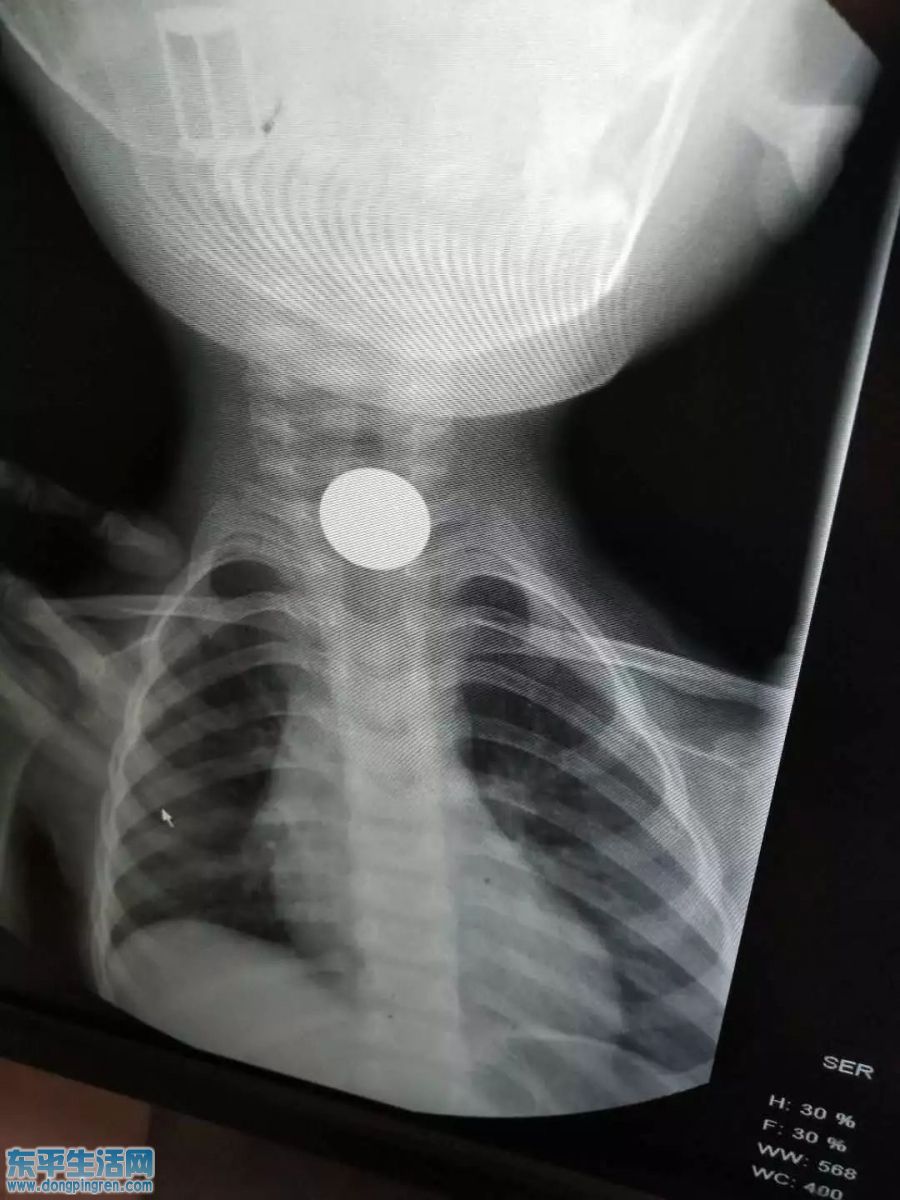

两岁男童因误吞一枚硬币,被紧急送到医院就诊,幸运的是医生仅用十分钟便将硬币取出,这是昨天发生在东平县人民医院的事。

3月20日下午,由于家长的疏忽,两岁男童不小心将一枚五角硬币吞了下去。下午16时许,孩子的奶奶和爸爸急忙将他送至东平县人民医院就诊,经透视检查,发现这枚硬币已经卡在了他的食管上端。在通过留置针输液后,男童出现了大量呕吐,县人民医院内镜中心主任刘富刚决定为其进行胃镜下取出术。为一个两岁的孩子做胃镜下取出术,必须要在全麻下进行。经内镜中心郑茂华、李大鹏两位麻醉师紧急会诊,并克服各种困难,做好各种突发预案后,为男童进行全麻,同时有七名医护人员全程监护,力争在最短的时间内将硬币取出。

经过近10分钟的精细操作,硬币被顺利取出。术后经仔细检查,男孩咽喉部位未见明显损伤。